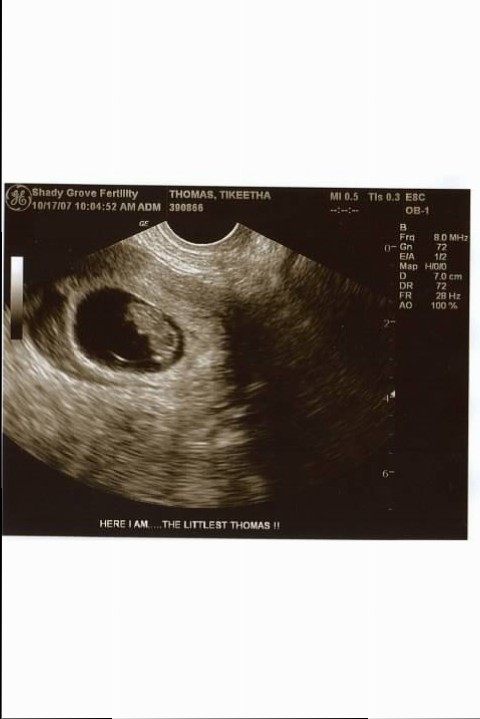

The sonographer inserted the trans-vaginal probe into my uterus and I laid there feeling helpless with tears running down my face and the sound of the machine in the background. I was praying hard. She said, “I don’t see the problem. There’s the fetus and there’s the heartbeat.” I couldn’t believe it. I asked, “Are you saying that my baby is still there?” She said, “Yes, look at the screen. The fluttering is the heartbeat. It’s strong.” I couldn’t stop crying and smiling and thanking God. As I was being rolled back into my room, I promised one thing. I would be like Hannah in the Bible and I would dedicate my son to God as long as He promised to protect his life and let me give birth. This was my vow.